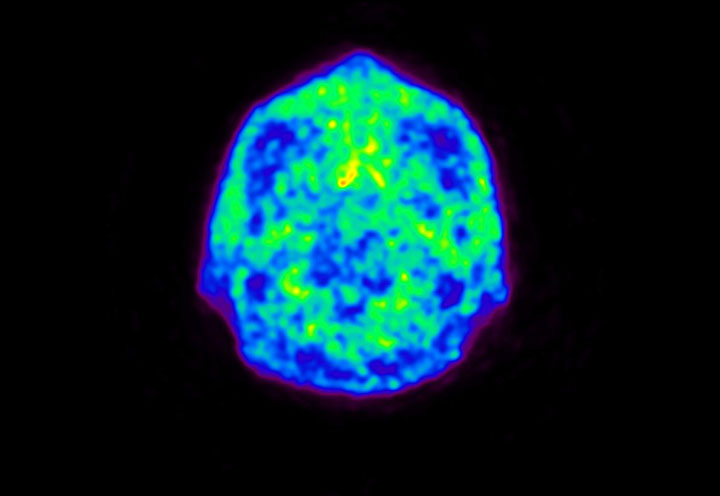

Head / Case5 : Amyloid

Coronal

Courtesy : Kindai University Hospital

- Imaging protocol

- Injected dose: 4.27 MBq/kg, 18F-Flutemetamol

- Uptake time: 99 minutes

- Scan time: 20 minutes